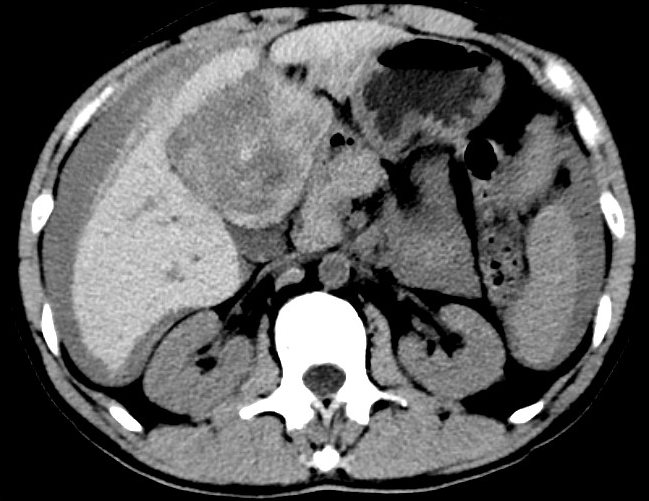

放下電話的白葦急赴消內(nèi)三搶救室會(huì)診,經(jīng)仔細(xì)查體、對(duì)患者腹部CT進(jìn)行詳細(xì)閱片、綜合評(píng)估患者后,考慮患者是肝占位破裂出血?;颊卟∏槭志o急、一刻也不容耽誤,需立刻急診行肝動(dòng)脈造影 栓塞術(shù)進(jìn)行止血治療,在與患者家屬溝通后,立即通知消化介入室準(zhǔn)備急診手術(shù)。

入手術(shù)室時(shí),患者神志迷糊,口唇干燥、重度貧血貌,心電監(jiān)護(hù)提示:心率140-160次/分,血壓70/43mmHg,這是失血性休克的表現(xiàn)!白葦快速建立靜脈通道緊急給予輸血,升壓,止血等液,立即給予肝動(dòng)脈造影,術(shù)中發(fā)現(xiàn)肝左葉疑似腫瘤病灶、病灶周圍血管分支有造影劑外溢,考慮血管破裂出血,迅速給予栓塞微球進(jìn)行肝動(dòng)脈栓塞。整個(gè)手術(shù)過程不足20分鐘,術(shù)后即刻患者心率降至100-110次/分、血壓升至90/60mmHg。

術(shù)后給予積極抗炎,止血,保肝、利尿等對(duì)癥治療,復(fù)查血常規(guī)提示活動(dòng)性出血停止后,在超聲引導(dǎo)下行腹腔穿刺引流術(shù),術(shù)后3天共引流出血性腹水約4000ml。患者經(jīng)復(fù)查各項(xiàng)指標(biāo)均趨于正常,復(fù)查CT提示腹腔積血已基本吸收,患者康復(fù)出院。